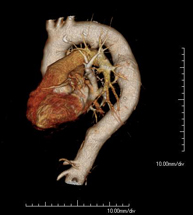

- Angio-TC Cardíaco o TC Cardíaco El angio-TC Cardíaco o Coronariografía no invasiva es una prueba diagnóstica que consiste en el estudio de las arterias del corazón o arterias coronarias mediante el empleo de un equipo de TC Multidetector de última generación y de un contraste yodado, obteniendo imágenes bi y tridimensionales. El TC Multidetector o TCMD permite una adquisición de imágenes tan rápida, que se pueden valorar las arterias coronarias con una alta precisión anatómica: estrechamientos o estenosis, calcificaciones, variantes anatómicas, etc., ya que gracias a su rapidez evita el artefacto que provoca el movimiento constante del corazón (tarda menos de diez segundos en adquirir unas 1000 imágenes). La información obtenida precisa de un tratamiento en estaciones de trabajo con programas especializados en la reconstrucción de las arterias coronarias que permiten valorar el número, la localización y las características de las lesiones. Toda esta información se obtiene de manera no invasiva: solo se requiere la punción de una vena periférica (en el brazo). Es necesario que la frecuencia cardíaca no supere los 75 latidos por minuto, por lo que algunos pacientes deberán realizar un tratamiento previo con un fármaco betabloqueante. El angio-TC Cardíaco o Coronariografía no invasiva es una prueba diagnóstica que consiste en el estudio de las arterias del corazón o arterias coronarias mediante el empleo de un equipo de TC Multidetector de última generación y de un contraste yodado, obteniendo imágenes bi y tridimensionales. El TC Multidetector o TCMD permite una adquisición de imágenes tan rápida, que se pueden valorar las arterias coronarias con una alta precisión anatómica: estrechamientos o estenosis, calcificaciones, variantes anatómicas, etc., ya que gracias a su rapidez evita el artefacto que provoca el movimiento constante del corazón (tarda menos de diez segundos en adquirir unas 1000 imágenes). La información obtenida precisa de un tratamiento en estaciones de trabajo con programas especializados en la reconstrucción de las arterias coronarias que permiten valorar el número, la localización y las características de las lesiones. Toda esta información se obtiene de manera no invasiva: solo se requiere la punción de una vena periférica (en el brazo). Es necesario que la frecuencia cardíaca no supere los 75 latidos por minuto, por lo que algunos pacientes deberán realizar un tratamiento previo con un fármaco betabloqueante.

- Angio TC cardíac L'Angio TC cardíac o la coronariografia no invasiva és una prova diagnòstica que consisteix en l'estudi de les artèries del cor o artèries coronàries mitjançant l'ús d'un equip de TC Multidetector d'última generació (64 corones o files de detectors) i de contrast iodat amb l'obtenció d'imatges bi i tridimensionals. El TC Multidetector 64 o TCMD64 permet una adquisició d'imatges tan ràpida que es poden valorar les artèries coronàries amb alta precisió anatòmica (estrenyiments o estenosis, calcificacions, variants anatòmiques, etc.), ja que, gràcies a la seva rapidesa, evita les falses imatges que provoca el moviment constant del cor (triga menys de deu segons en adquirir unes 1000 imatges). La informació obtinguda d'un tractament en estacions de treball amb programes especialitzats en la reconstrucció de les artèries coronàries que permeten valorar el nombre, la localització i les característiques de les lesions. Tota aquesta informació s'obté de manera no invasiva: només es necessita la punció d'una vena perifèrica (en el braç). És necessari que la freqüència cardíaca no superi els 75 batecs per minut, per això els pacients han de realitzar un tractament previ amb un fàrmac betabloquejant. L'Angio TC cardíac o la coronariografia no invasiva és una prova diagnòstica que consisteix en l'estudi de les artèries del cor o artèries coronàries mitjançant l'ús d'un equip de TC Multidetector d'última generació (64 corones o files de detectors) i de contrast iodat amb l'obtenció d'imatges bi i tridimensionals. El TC Multidetector 64 o TCMD64 permet una adquisició d'imatges tan ràpida que es poden valorar les artèries coronàries amb alta precisió anatòmica (estrenyiments o estenosis, calcificacions, variants anatòmiques, etc.), ja que, gràcies a la seva rapidesa, evita les falses imatges que provoca el moviment constant del cor (triga menys de deu segons en adquirir unes 1000 imatges). La informació obtinguda d'un tractament en estacions de treball amb programes especialitzats en la reconstrucció de les artèries coronàries que permeten valorar el nombre, la localització i les característiques de les lesions. Tota aquesta informació s'obté de manera no invasiva: només es necessita la punció d'una vena perifèrica (en el braç). És necessari que la freqüència cardíaca no superi els 75 batecs per minut, per això els pacients han de realitzar un tractament previ amb un fàrmac betabloquejant.